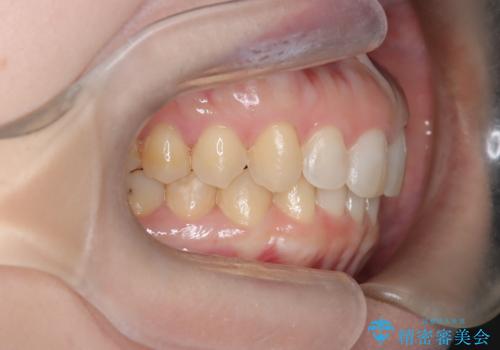

【インビザライン】前歯の凸凹を治したい。

- 前歯の凸凹を主訴に来院されました。

深い噛み合わせも同時に治療を行う計画を立て、インビザラインを使用して歯並びの改善を行うことができました。

叢生改善のために遠心移動とIPRを行なっています。